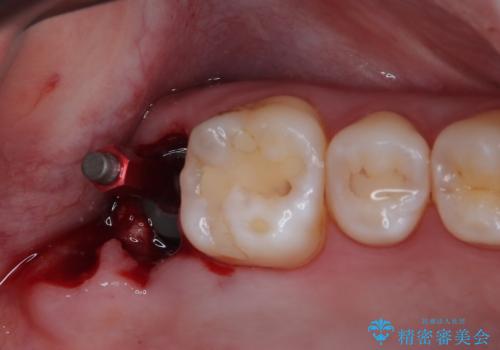

右上のインプラント治療は、1DAYインプラント治療(抜歯即時埋入・即時荷重)の適応となりましたので、通常3回必要な外科処置の回数を1回に集約させることができました。